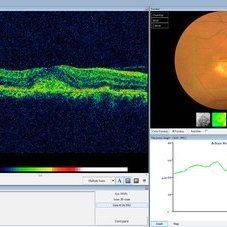

Best Disease Best DiseaseMar 9 2013 by Hamid Ahmadieh, MD OCT of the left eye of a 49-year-old man with decreased VA due to advanced Best disease. Photographer: Soodabeh Fooladin, Negah Eye Center, Tehran Imaging device: Heidelberg Spectralis Condition/keywords: Best disease, optical coherence tomography (OCT)